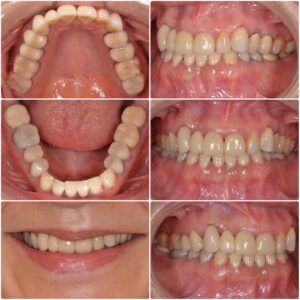

セラミック治療希望 20代男性 2026.2.24

主訴・術前 オールセラミック希望 術後の患者様の感想 忙しく、なかなか通えていませんでしたが、とても丁寧に治療をしてくださり満足しています。 また、院長先生やスタッフの皆様が優しく対応してくださり助かりましたありがとうご…